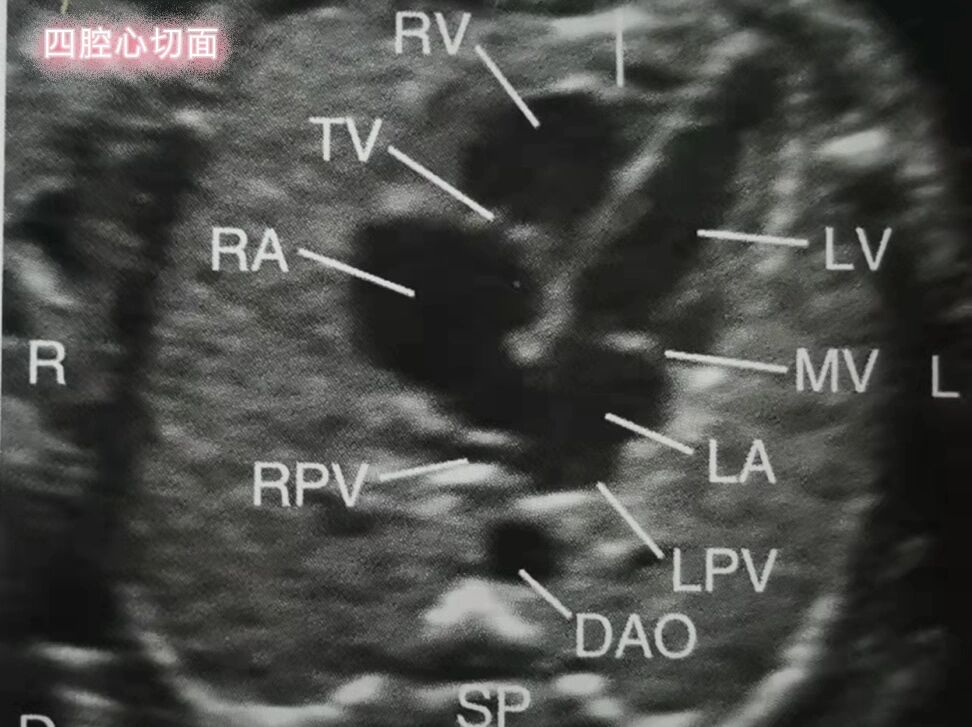

四腔心切面图

胎儿心脏—四腔心切面 1,心脏的2/3位于左侧胸腔内,心尖指向左前方